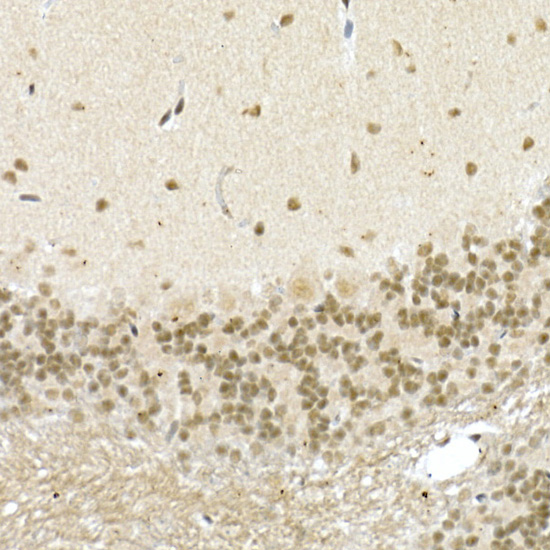

Immunohistochemistry analysis of paraffin-embedded Mouse brain using CREB1 at dilution of 1:50 (40x lens).